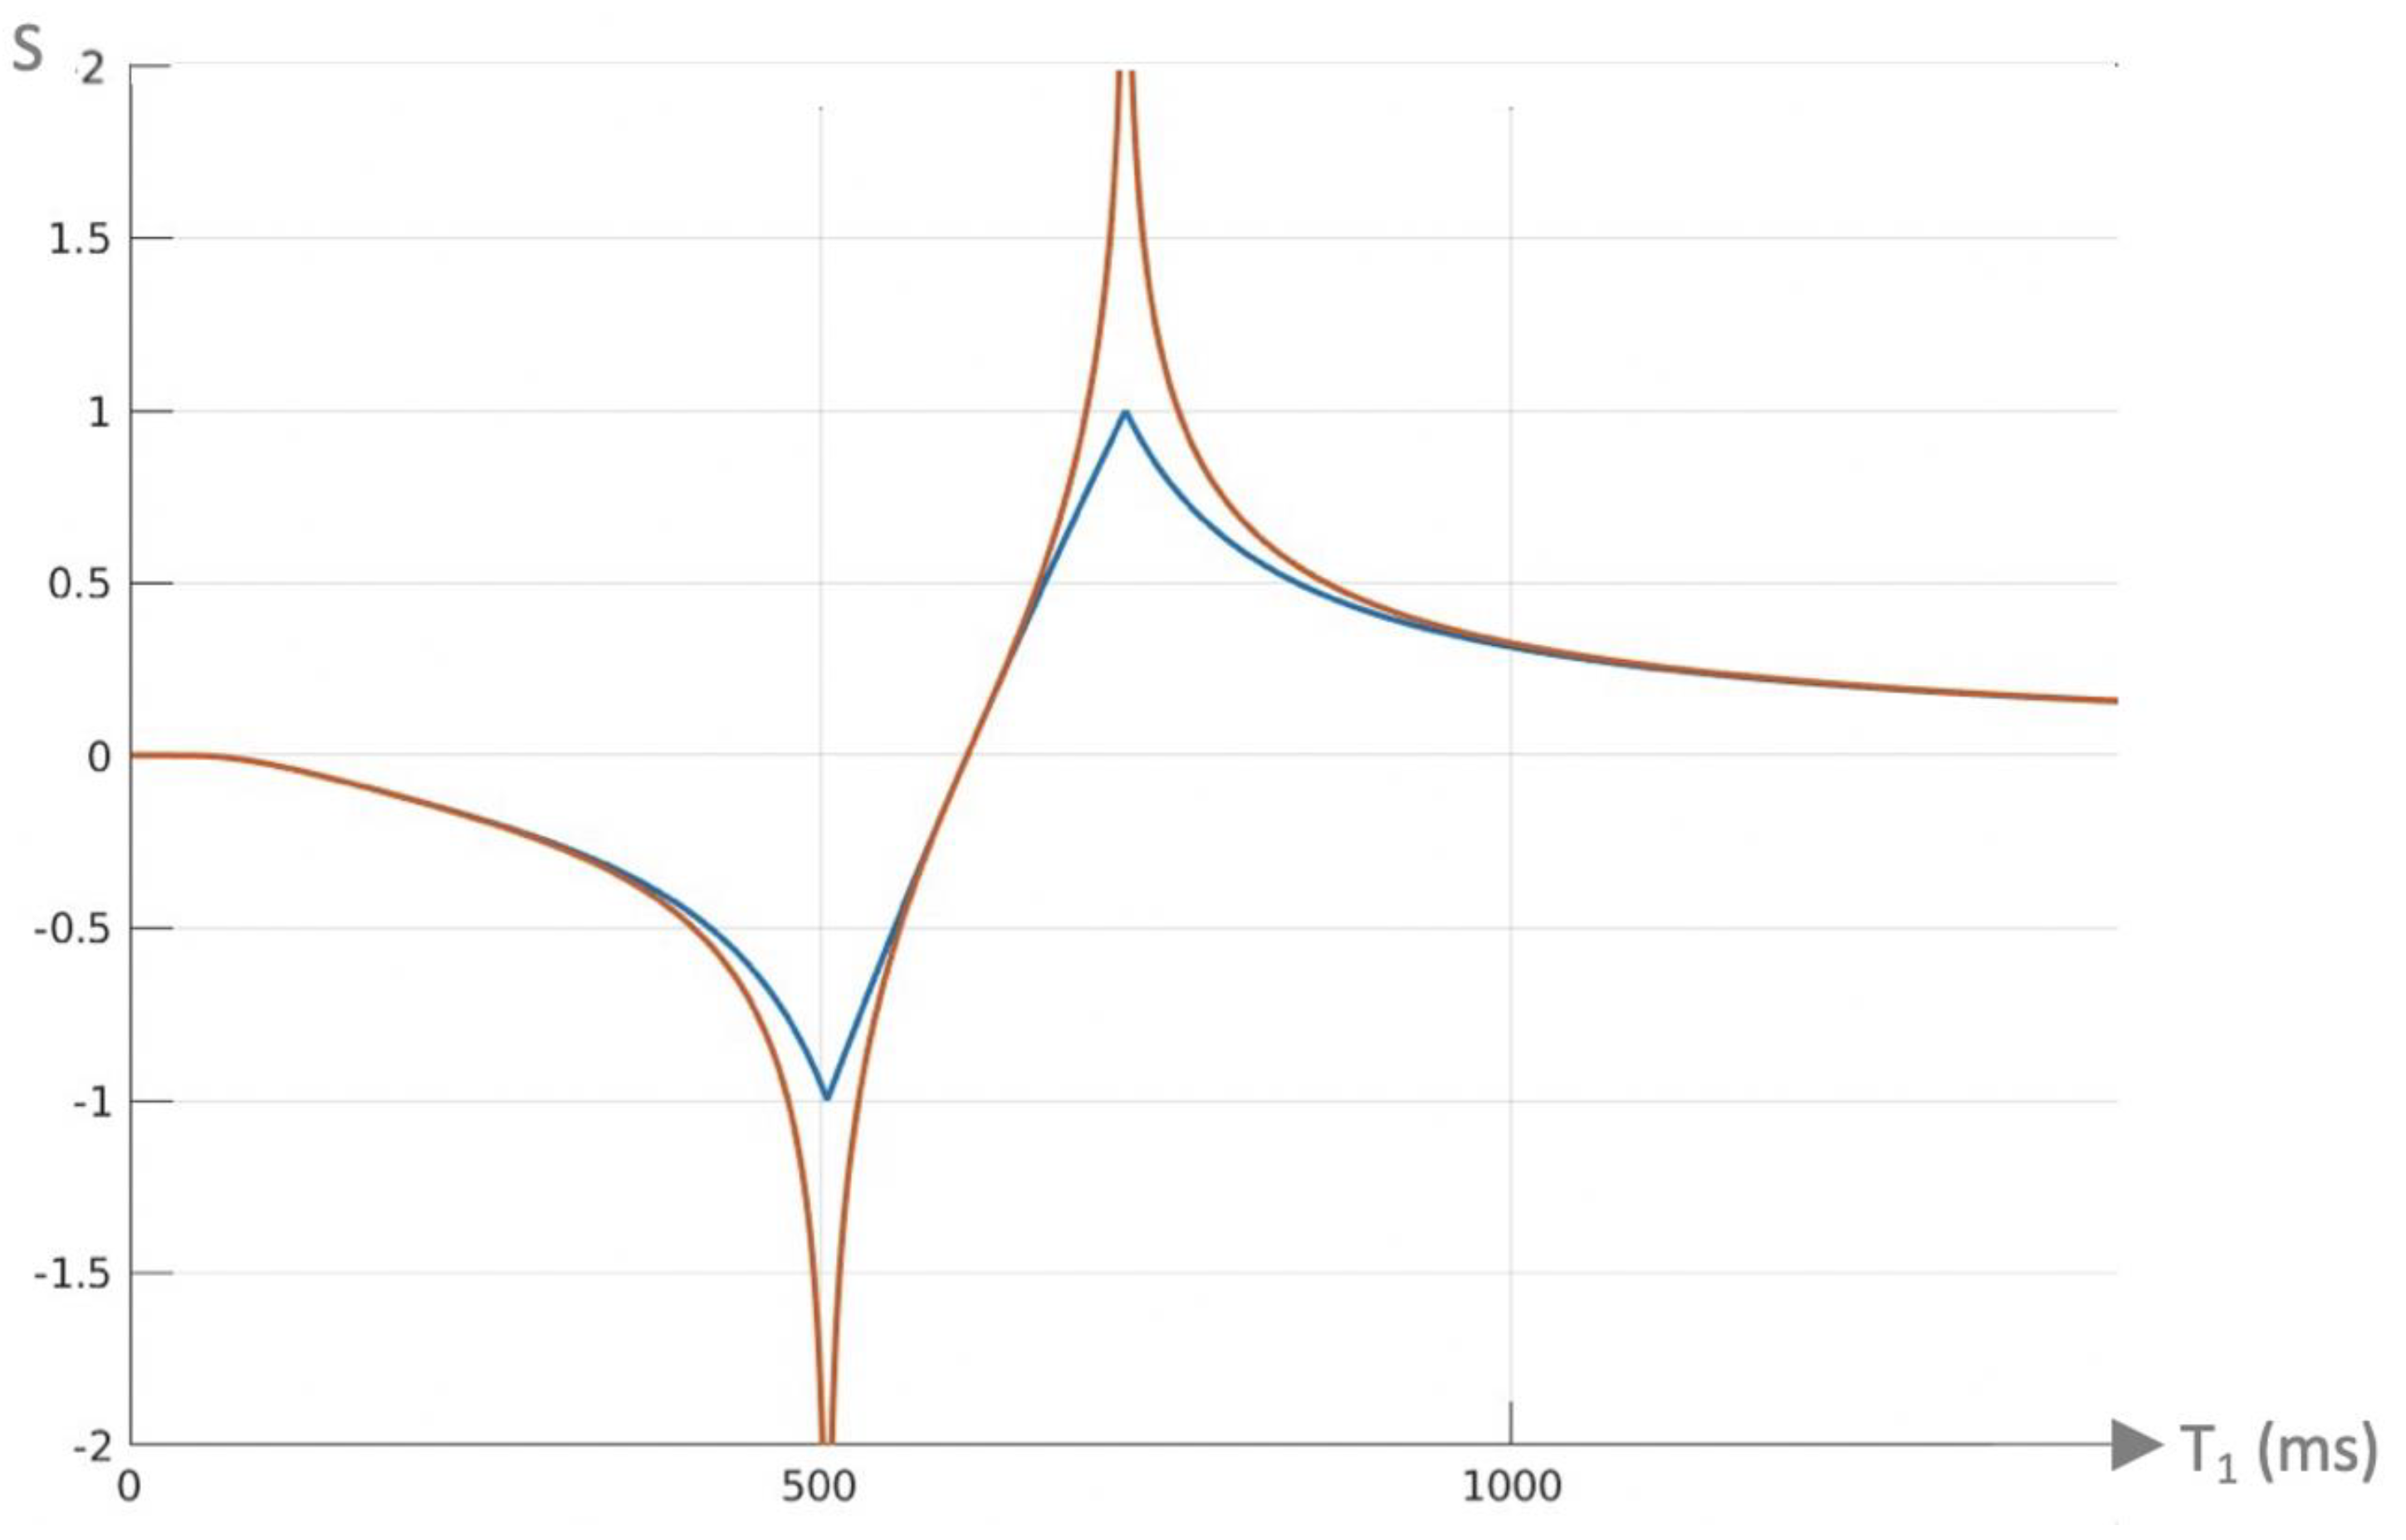

2. Basic Physics

2.4. Log then Subtracted Inversion Recovery (lSIR) Sequences

| 9 | lSIR | SlSIR = ½(ln STIs − ln STIi) | Figure 4 |

| 12 | lSIR, dSIR † | SlSIR = atanh SdSIR | Figure 4 |